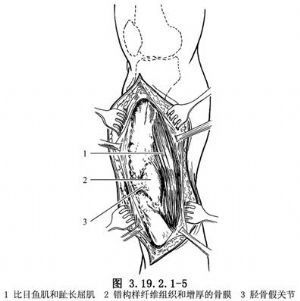

切開皮下和深筋膜,向前後遊離皮瓣,保護大隱靜脈和隱神經,顯露假關節和病變組織(圖3.19.2.1-5)。骨膜外仔細分離並向後牽開比目魚肌和趾長屈肌,以顯露後側的病變組織。徹底切除包圍假關節的增厚纖維組織和骨膜(圖3.19.2.1-6)。